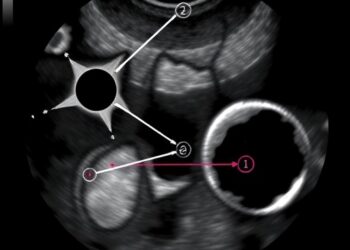

In the realm of pediatric medicine, acute abdominal pain remains one of the most prevalent issues that healthcare professionals encounter. ...